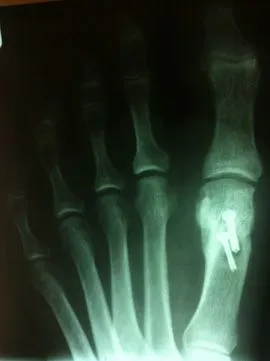

During surgical correction of the bunion a v-shape bone is made in most cases to translate the head of the 1st metatarsal laterally which creates an overhang of bone from the previous position of the bone (pictured left). The overhang is remove and the new position of the bone is held with some type of fixation which varies from screws, staples, or pins which is the case here. The pin is buried left in permanently (pictured right).

X-rays demonstrating correction of bunion deformity with the great toe deviated laterally (left image) and notice the position of the sesamoid bones which are the small round bones near the joint. The post-surgical film (right image) depicts alignment of the great toe significantly improved and the position of the sesamoid is underneath the 1st metatarsal head where it should be. This is a case where two surgical screws were used to fixate the correction.